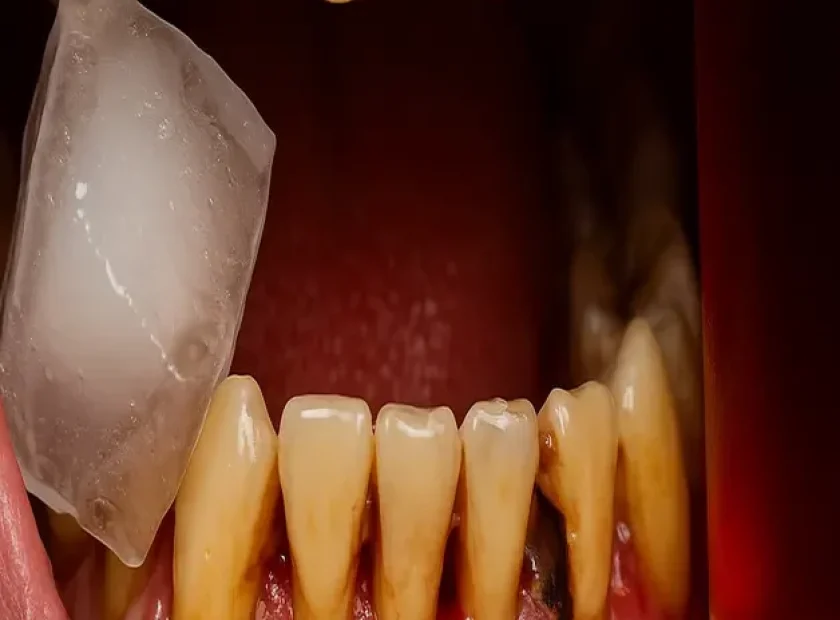

اضطراب شدید بیمار هنگام نزدیک شدن سرنگ بیحسی

همچنین وضعیت دندان و لثه نقش تعیینکننده دارد؛ التهاب لثه، حساسیت دندانی یا پوسیدگی فعال میتواند حتی در درمانهای بدون آمپول هم احساس ناخوشایند ایجاد کند.